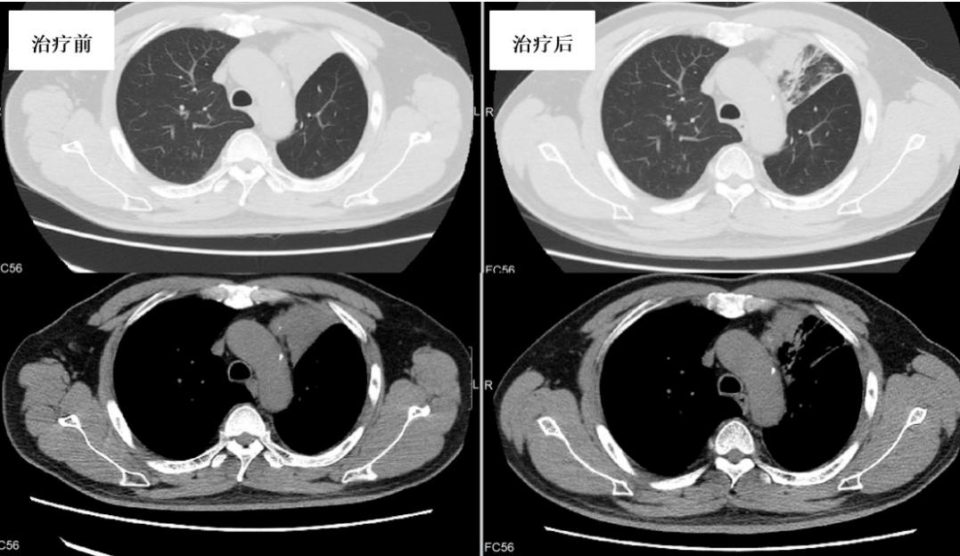

CT(图9):双肺散在病灶,左上肺为主。双侧多发肋骨、胸骨、双侧肩胛骨、胸3、11椎体破坏并周围软组织肿块形成,多发肋骨病理性骨折、右侧胸壁及正中前胸壁脓肿形成。

治疗方案及转归:利福平、乙胺丁醇、阿奇霉素、利奈唑胺;并辅以支气管镜下介入治疗(套扎、激光、钳取、冷冻等)。治疗2个月后复查CT及支气管镜病灶较前吸收(图9、图10)。

图9. 治疗2个月后左上肺病灶较前吸收